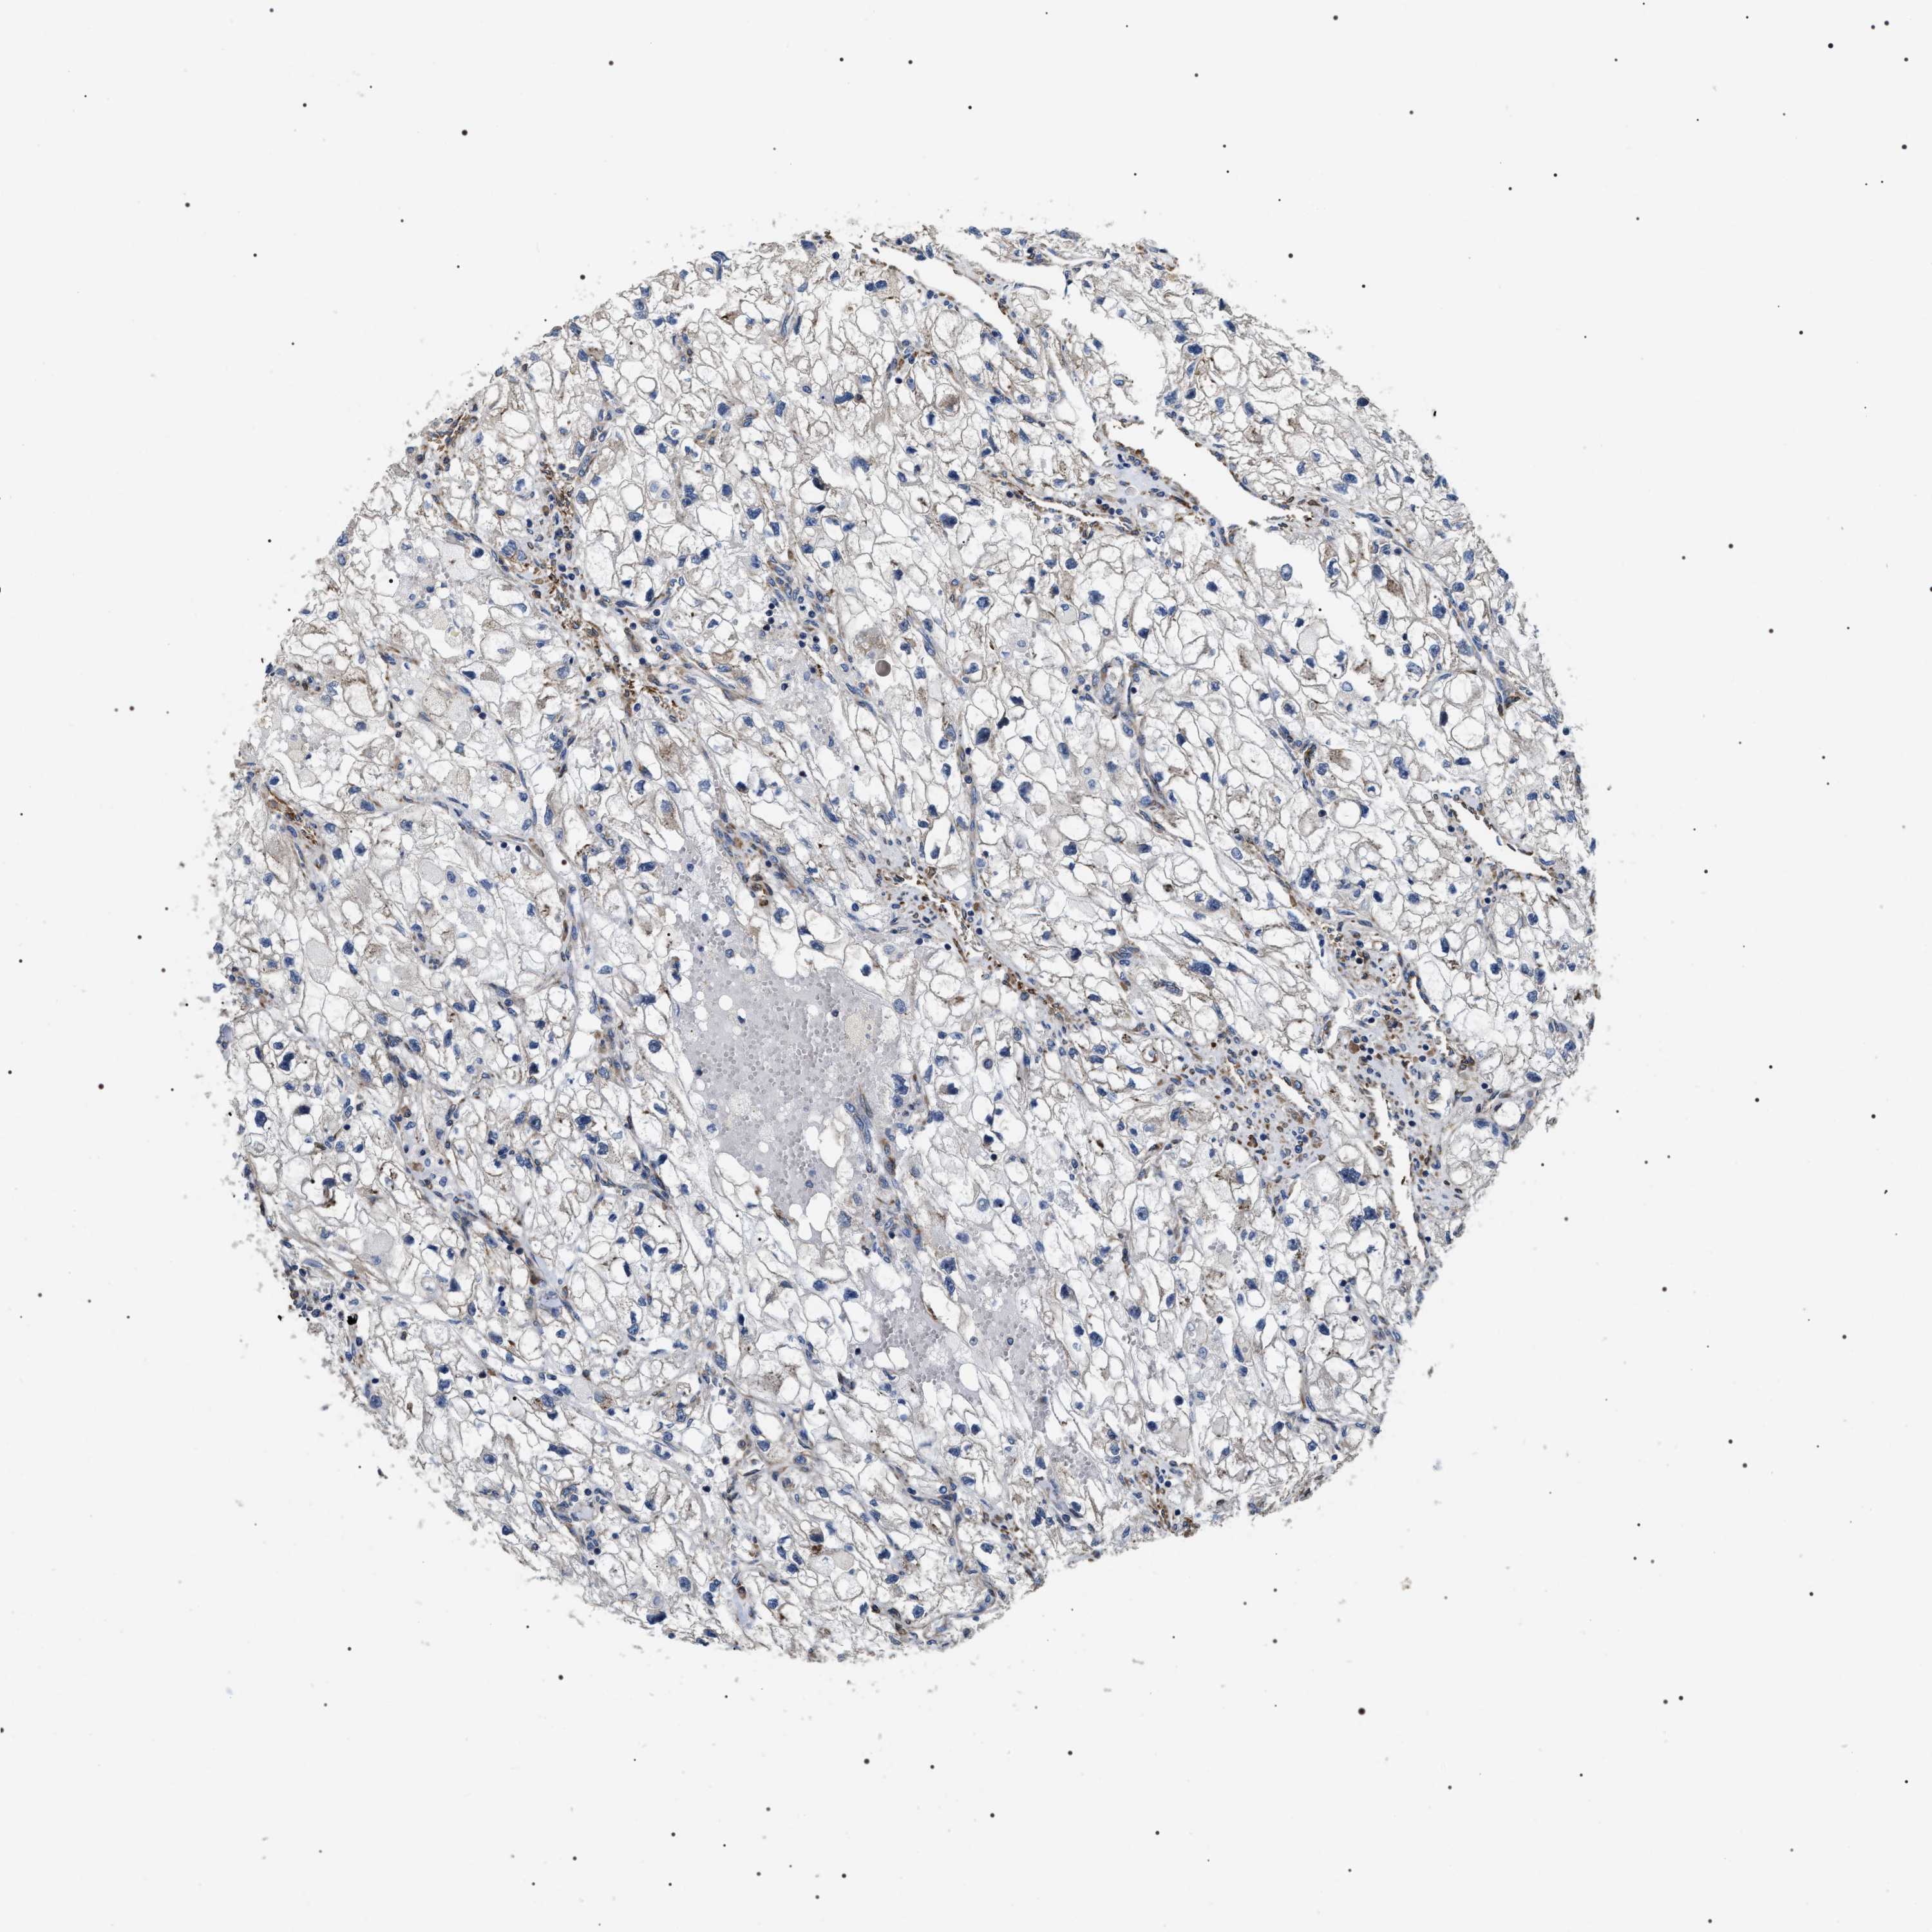

KIDNEY RENAL CLEAR CELL CARCINOMA (VALIDATION) - Interactive survival scatter ploti

The Survival Scatter plot shows the clinical status (i.e. dead or alive) for all individuals in the patient cohort, based on the same data that underlies the corresponding Kaplan-Meier plots. Patients that are alive at last time for follow-up are shown in blue and patients who have died during the study are shown in red.

The x-axis shows the expression levels (FPKM) of the investigated gene in the tumor tissue at the time of diagnosis. The y-axis shows the follow-up time after diagnosis (years). Both axes are complimented with kernel density curves demonstrating the data density over the axes. The top density plot shows the expression levels (FPKM) distribution among dead (red) and alive patients (blue). The right density plot shows the data density of the survived years of dead patients with high and low expression levels respectively, stratified using the cutoff indicated by the vertical dashed line through the Survival Scatter plot. This cutoff is automatically defined based on the FPKM cutoff that minimizes the p-score. The cutoff can be changed by dragging the vertical line or by entering a cutoff value in the square labeled "Current cut-off".

Under the Survival Scatter plot the p-score landscape (black curve; left axis) is shown together with dead median separation (red curve; right axis). Dead median separation is the difference in median mRNA expression between patients who have died with high and low expression, respectively. It is calculated as follows: median FPKM expression of dead patients with high expression - median FPKM expression of dead patients with low expression. This is intended to aid the user in visually exploring custom cutoffs and the associated p-scores and dead median separation.

Individual patient data is displayed and can be filtered by clicking on one or more of the category buttons on the top of the page. Categories describing expression level and patient information include: high, low, alive, dead, female, male and tumor stages. The scale of the x-axis can be toggled between linear and log-scale by clicking on the "x log" button. Mouse-over function shows TCGA ID, patient information and mRNA expression (FPKM) for each patient.

& Survival analysisi

Kaplan-Meier plots summarize results from analysis of correlation between mRNA expression level and patient survival. Patients were divided based on level of expression into one of the two groups "low" (under cut off) or "high" (over cut off). X-axis shows time for survival (years) and y-axis shows the probability of survival, where 1.0 corresponds to 100 percent.

ZC3HAV1L is not prognostic in Kidney Renal Clear Cell Carcinoma (validation)

: 9.84

N/A

Average pTPM 14.8

Number of samples 100